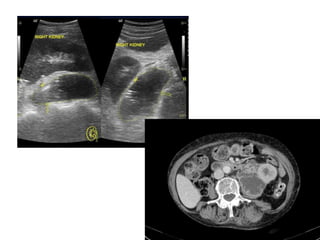

 USG- dilatation of the PCS,

echogenic collecting system

debris, fluid-fluid levels within

the collecting system, and occ.

incomplete (dirty) echoes of

collecting system gas.

 Echogenic debris- sensitivity of

90%, specificity of 97%, and

accuracy of 96% in the

diagnosis of pyonephrosis

versus simple hydronephrosis

 CT

- thickening of the renal pelvic wall

(>2 mm),

- parenchymal or perinephric

inflammatory changes,

- dilatation and obstruction of the

collecting system,

- higher attenuation values of the

fluid within the renal

collecting system, and

- layering of contrast material above

and anterior to the purulent fluid on

excretory studies .